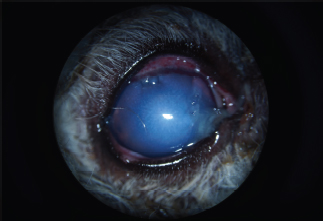

The AC was stabilized by intracameral injection of a viscoelastic gel (hyaluronic acid 1.6%, Ophteis Bio) by a perforating keratotomy port at 12 o’clock. As the base of the claw was crenelated, it was not possible to remove it through the site of penetration, which is why another perforating keratotomy port was made at 10 o’clock. The claw was grasped with Bonn’s pliers and then gently removed. The entry point of the claw and the 10 o’clock port were sutured by single stitches using polyglactin 9/0 (Vicryl 9/0). The pupil was then dilated by injection of 1 ml of epinephrine at a concentration of 1 mg/ml into the AC. The anterior lens was ruptured, and a heterogeneous traumatic cataract had already developed (Fig. 2). The lens was, therefore, removed by phacoemulsification via the port at 12 o’clock. After removal of the masses by irrigation/aspiration, the tear of the anterior capsule was shaped before injection of an implant (PFI 4X, Medicontur). The keratotomy port at 12 o’clock was sutured by three single stitches with Vicryl 9/0 after the removal of residual viscoelastic material by suction irrigation. At this stage of the surgery, a tear of the endothelium and Descemet membrane was visible, following the most likely trajectory of the claw into the AC (Fig. 3). Water bubbles were already forming in the corneal stroma. An injection of 0.25 μg of tissue plasminogen activator (Actilyse®, BOEHRINGER INGELHEIM) was performed in the AC at the end of the intervention to limit postoperative fibrinous collection. The claw was sent to the laboratory for bacteriological analysis.

Fig. 2. Appearance of the eye after claw excision, corneal reconstruction, and pharmacological mydriasis. The tear of the anterior capsule is large and complex. The architecture of the lens is turned upside down.